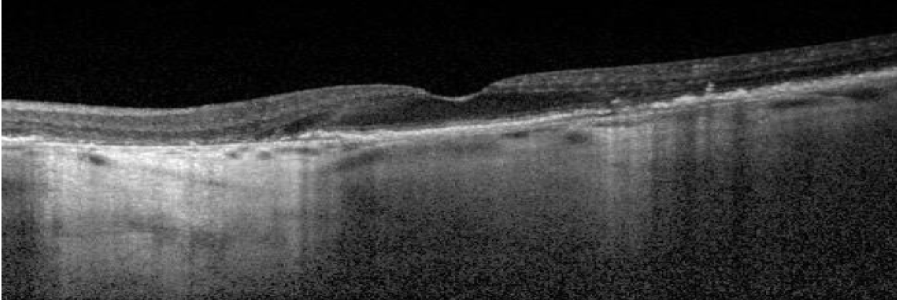

Baseline

BCVA: 6/7.5

Choroidal hypertransmission defect is a sign of atrophy.

Year 4

BCVA: 6/15

Lesion has grown closer to the fovea as shown by larger area of hypertransmission on OCT. However, BCVA has only declined slightly as fovea is still intact.

Images courtesy of Dr Mohammad Rafieetary, OD, Charles Retina Institute.